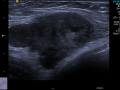

Biópsia percutânea de fragmento de nódulo de mama guiada pela ultrassonografia

Abr de 2020.

9.244

diagnóstico

Mastologia

Saúde da mulher

Ultrassonografia